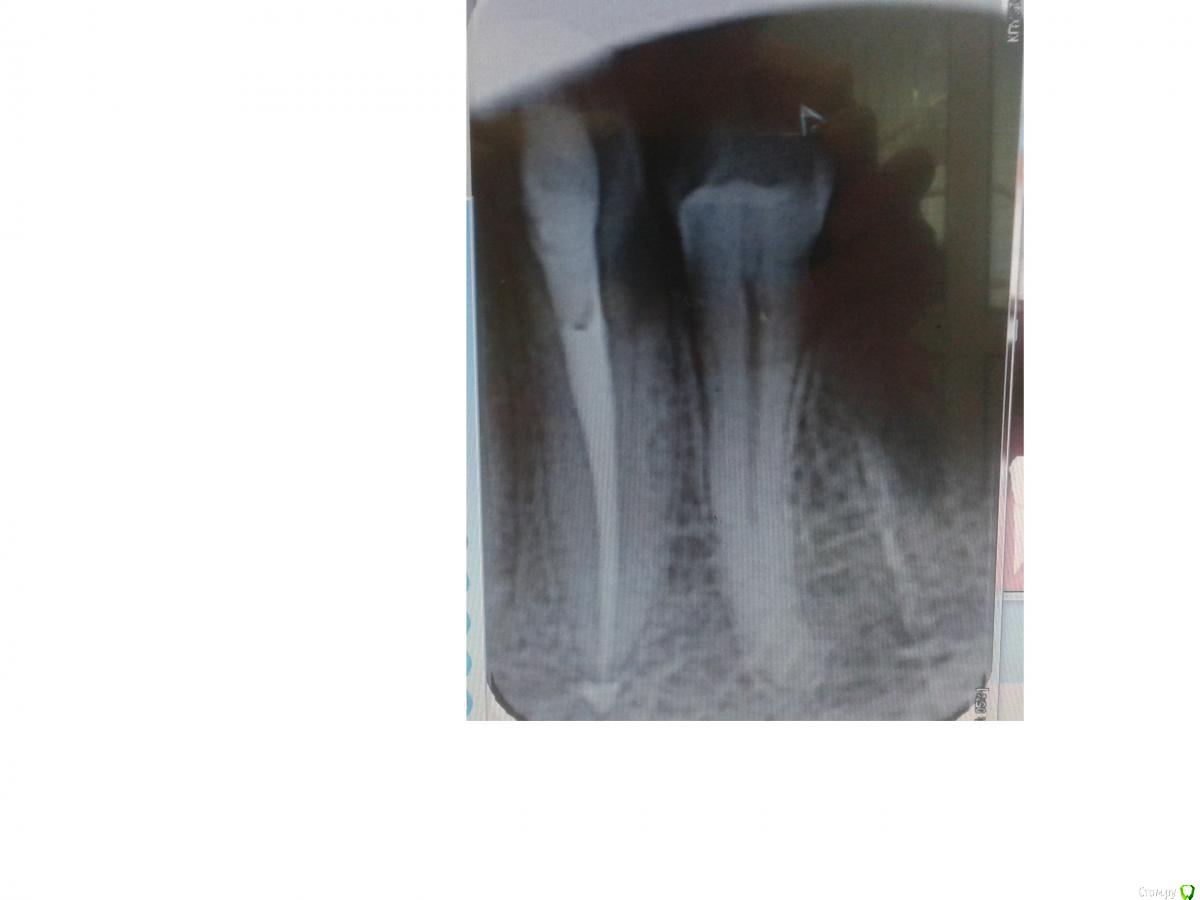

mariskus71 Опубликовано 21 августа, 2015 Поделиться Опубликовано 21 августа, 2015 (изменено) Зуб лечили в общей сложности три месяца.Три недели назад запломбировали канал фосфадентом.Врач сказала,что специально вывела его за верхущку корня и сказала,что он рассосётся.Зуб париодически пульсирует и побаливает при постукивании по нему.Нимесил боли снимает.Действительно ли нужно потерпеть и подождать,когда выведенный материал рассосётся и вообще фосфадент может рассосаться?И ещё заметила на снимке пустоту под пломбой.Что это такое.Простите, но врач уехал,а я со своим зубом осталась.Может оцените работу.Врач долго мучалась со мной. Изменено 21 августа, 2015 пользователем mariskus71 Ссылка на комментарий

St. Опубликовано 21 августа, 2015 Поделиться Опубликовано 21 августа, 2015 Объем выведенного материала небольшой. Это не страшно. Что было с зубом и почему столько времени лечили? Неприятные ощущения со временем сейчас уменьшаются? Ссылка на комментарий

mariskus71 Опубликовано 22 августа, 2015 Автор Поделиться Опубликовано 22 августа, 2015 (изменено) Объем выведенного материала небольшой. Это не страшно. Что было с зубом и почему столько времени лечили? Неприятные ощущения со временем сейчас уменьшаются?Зуб впервые депульпировали в мае месяце(зуб реагировал на вертикальную перкуссию,сделали снимок-на снимке со стороны 34 зуба определили как бы скрытую полость,хотя при осмотре зондом не определили,)Решили депульпировать.После этого зуб практически не беспокоил.Единственный неприятный момент-через три недели после лечения зуб стало распирать от горячего(это была не боль,но он как будто бы немел,потом проходил)Врч сделала снимок-нашла полость под пломбой,рещила снять пломбу.Пломбу сняли,а ощущение на горячее осталось.Врач распломбировала зуб и поставила турунду с звгенолом.Вот с этого момента всё и началось.Зуб стал реагировать на горячее и пульсировать..Турунду поменяли на метапекс(улучшений не было)Потом поменяли на каласепт(ни чего)Я поменяла врача,так как она сказала,что не знает что делать дальше.Второй врач сделала КТ и там был найден дополнительный канал(из основного выходит небольшой,который потом так же входит в него)Прочистили, и три раза с промежетками дней в 10 промывали горячим раствором гипохлогрда(концлагерь отдыхает)Закладывали после гипохлорида лидермикс.И вот 3 мая запломбировали фосфадентом.Посмотрите пожалуйста ещё разок.Я здесь скидывала фото ещё врачу.Он определяет ещё один канал (со стороны 34 зуба-между 34 и 33 полость и из этой полости выходит канал???? Предупрежу сразу-зуб немного развёрнут и насколько я могу понять,то такой же канал расположен и спротивоположной стороны.Может это просто тень?)Есть ещё снимки,если Вас заинтересует-выложу.По поводу неприятных ощущений-пока всё терпимо,я полощу содой с солью и 2-3 кап.йода,нимесил пила раза два.Спасибо. Изменено 22 августа, 2015 пользователем mariskus71 Ссылка на комментарий

St. Опубликовано 24 августа, 2015 Поделиться Опубликовано 24 августа, 2015 (изменено) Если Вы об этом - то это не канал , а контуры костной перегородки между этим и соседним зубом. А снимки выкладывайте, посмотрим. Изменено 24 августа, 2015 пользователем St. Ссылка на комментарий

mariskus71 Опубликовано 25 августа, 2015 Автор Поделиться Опубликовано 25 августа, 2015 (изменено) Если Вы об этом - то это не канал , а контуры костной перегородки между этим и соседним зубом. А снимки выкладывайте, посмотрим.Спасибо Вам большое,сняли груз с души,а то я уж думала,что дополнительный канал не запломбировали.Выкладываю снимки.Первый снимок был сделан после пломбировки временным каласептом.Второй перед пломбировкой прошли канал и нашли дополнительный.А на последнем врач отметил непонятные участки (со вторым я поняла,а вот с первой цифоркой то же непонятно)Спасибо Изменено 25 августа, 2015 пользователем mariskus71 Ссылка на комментарий

St. Опубликовано 25 августа, 2015 Поделиться Опубликовано 25 августа, 2015 Пожалуйста) По снимку с инструментами всё хорошо. По тому который после пломбировки - тоже.Что врач хотел отметить - не знаю.Как сейчас ведет себя зуб? Неприятные ощущения уменьшаются? Ссылка на комментарий